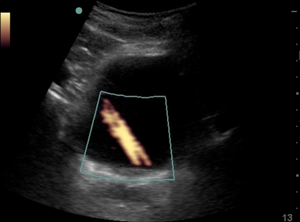

- Color over the inferior border can demonstrate ureteral jets

- Twinkle Sign: rapid alternation of color immediately behind a stationary echogenic object, acquiring a false appearance of movement

- Can indicate stone in the UVJ

- Twinkle Sign: rapid alternation of color immediately behind a stationary echogenic object, acquiring a false appearance of movement

- Lack of jet on one side can indicate ureteral obstruction